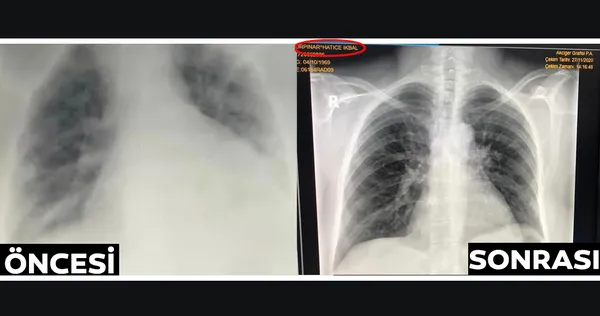

Bunu ben yenerim Allah'ın izniyle deyip kendimi bakıma çektim. Vitaminler, gıda takviyeleri, kekik yağı, aklınıza ne geliyorsa denedim. Ateşim düştü ve ağrılarım azaldı. Ardından arkadaşımın söylediği bir şey içtim. İkinci gün nabzım inanılmaz hızlandı. Çok yoruldum ve hastanelik oldum. Doktorlar çok kızdı. Hatta içlerinden biri 'Kim söylediyse gidin o tedavi etsin sizi" dedi. Hastayken her şeyi yapmak istiyorsunuz ama her ilaç, bitki vs. herkese iyi gelecek diye bir şey yok. Sizde kronik veya bilmediğiniz bir hastalık olabiliyor ve içtiğiniz şey size dokunabiliyor. Ardından annemin de ateşi çıkınca kahroldum. Hastaneye gitmemek için direnmekle hata ettim. Çok geç kalmıştım, ciğerlerim tamamen zarar görmüştü. Aynı gün annemi de başka bir hastaneye kaldırmışlardı. Korkunç günlerdi…